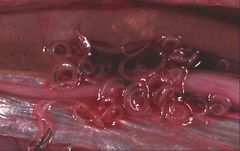

Unidentified Anisakidae (Ascaridina: Ascaridoidea) | |

- The Anisakidae are also called the "marine mammal ascarids". The larvae of these worms cause anisakiasis when ingested by humans in raw or insufficiently cooked fish, but do not reproduce in humans.